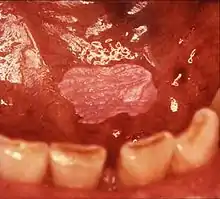

Leukoplakia on the inside of the cheek.

Leukoplakia is a white patch on a inside of the mouth, which cannot be rubbed off.[8] It is associated with an increased risk of cancer.[4][5] The edges of the lesion are typically abrupt and the lesion changes with time.[4][6] Advanced forms may develop red patches.[6] There are generally no other symptoms.[9] It usually occurs within the mouth, although sometimes mucosa in other parts of the gastrointestinal tract, urinary tract, or genitals may be affected.[10][11][12]